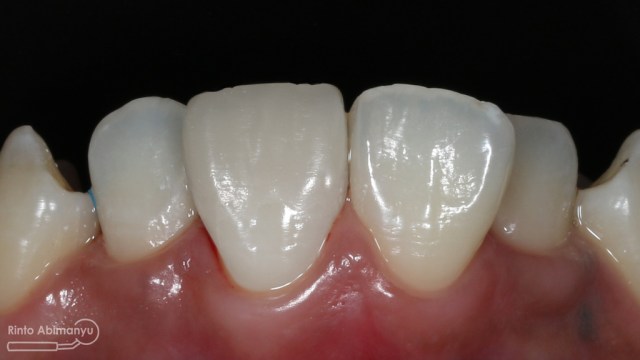

Begini hasil akhir setelah sementasi crown…

Foto klinis setelah pemasangan crown

Alhamdulillah pasien nya senang sekali…. dia puas dan saya pun senang karena dapat memenuhi keinginan pasien…..